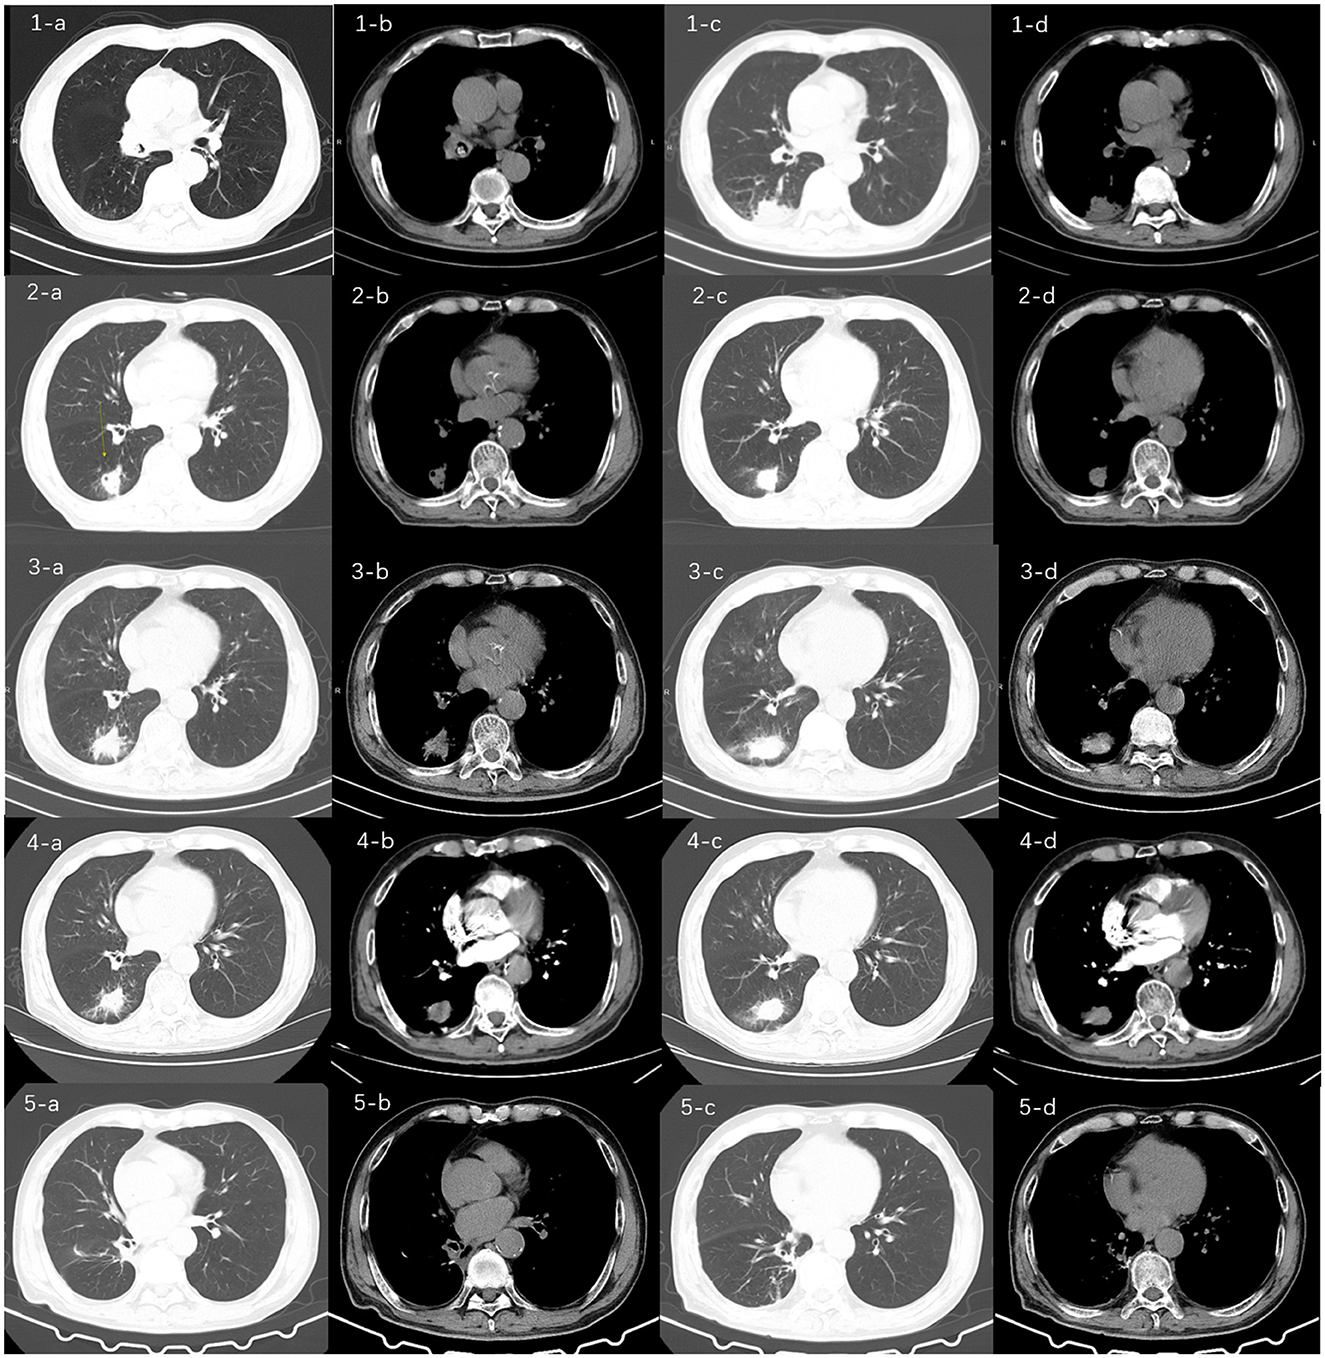

Abstract Background: Actinomyces infections tend to involve the head and neck, while lung infections are rare, and fatal hemoptysis due to pulmonary actinomycosis is even rarer. Case presentation: A 74-year-old male patient who presented with a cough with intermittent hemoptysis for 17 months was admitted to the hospital for the fourth time on June 24, 2024. At the first visit , a computed tomography scan of the chest revealed a high-density shadow in the right middle bronchus and an infected lesion in the lower lobe of the right lung. Hemoptysis was temporarily relieved after bronchoscopic removal of the foreign body and anti-infective treatment. Four months later, the patient was readmitted to the hospital due to a recurrence of hemoptysis. CT showed a lesion in the right lower lobe of the lung with cavitation, and bronchoscopy showed no abnormality. The pathology of percutaneous lung puncture biopsy suggested acute and chronic inflammation, and the patient was discharged under oral treatment with moxifloxacin. Four months later, the patient was admitted to the hospital for the third time because the hemoptysis volume had increased to 50 mL/day. Digital subtraction angiography-guided bronchial artery embolization was performed, and hemoptysis was controlled after the operation. Six months later, the patient was re-admitted to the hospital because of sudden hemoptysis as an emergency. Various medications were ineffective in stopping the hemoptysis, and the hemoptysis recurred,with a sudden drop in blood oxygen saturation level to 82%. Emergency bronchoscopic balloon occlusion was performed to stop bleeding, and right lower lobectomy was performed after multidisciplinary consultation. Postoperative pathology showed that the lung tissue was accompanied by tracheal dilatation, pus accumulation, and inflammatory granulomatous changes, with positive periodic acid Schiff staining, supporting actinomycetes infection. The patient continued anti-actinomycosis treatment for 1 month after surgery, and his condition stabilized after eight months of follow-up. Conclusions: Imaging of pulmonary actinomycosis is easily confused with tuberculosis and tumors and is difficult to diagnose. Pulmonary actinomycosis should be considered in patients with a lung mass shadow and recurrent hemoptysis. When life-threatening hemoptysis complicates pulmonary actinomycosis, surgical resection may effectively control the condition and improve the prognosis.